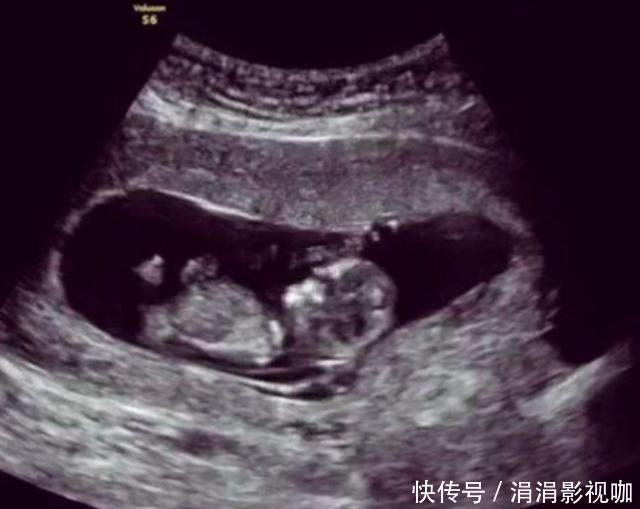

案例小吕和妻子结婚后日子就过得非常的和美,在别人的眼里他们就是模范夫妻的典范,在结婚后不久妻子就怀孕了,小吕也是非常的激动和开心,并且在日常生活中对于怀孕的妻子更是无微不至的照顾着,每一次妻子做产检,小吕都要亲自去陪伴。这天小吕又要陪着妻子去医院产检,头天晚上俩人还在一起数着胎动畅想着孩子的模样和未来,结果到了医院,门诊护士在给妻子听胎动的时候神情变得非常的紧张,还让旁边的护士赶紧去叫来了主治医生,然后就推着妻子进入了手术室,小吕知道情况不妙,可能是妻子和孩子出问题的。

小吕一直在产科的手术之外焦急的等待着,过了很长时间,妻子的主治医生终于出来了,小吕马上上前询问妻子和孩子的情况“医生,我的妻子和孩子怎么了?她们怎么样了?”医生回答说“现在胎儿的状态不是很好,需要引产,你赶紧准备一下并且办理下住院手续吧。”小吕当时就懵了,妻子再有2周就是预产期了,怎么却突然要引产了呢?

分析医生做引产的时候,发现胎儿并没有出现脐带绕颈的情况,并且胎位什么的也很正常,但是为什么胎儿就没有了心跳呢?在做完手术后,妻子被推回了病房,夫妻俩面面相觑都是一脸愁容,家里还放着一堆为孩子准备的东西,但是现在孩子却胎死腹中了,这样的事情换了谁肯定都是很难接受得了的。但是没有办法,就算是现在医疗水平如此高,对于“胎死腹中”的事情依然是没有任何办法解决不了,甚至都没有答案,一个新的生命就这么戛然而止了。